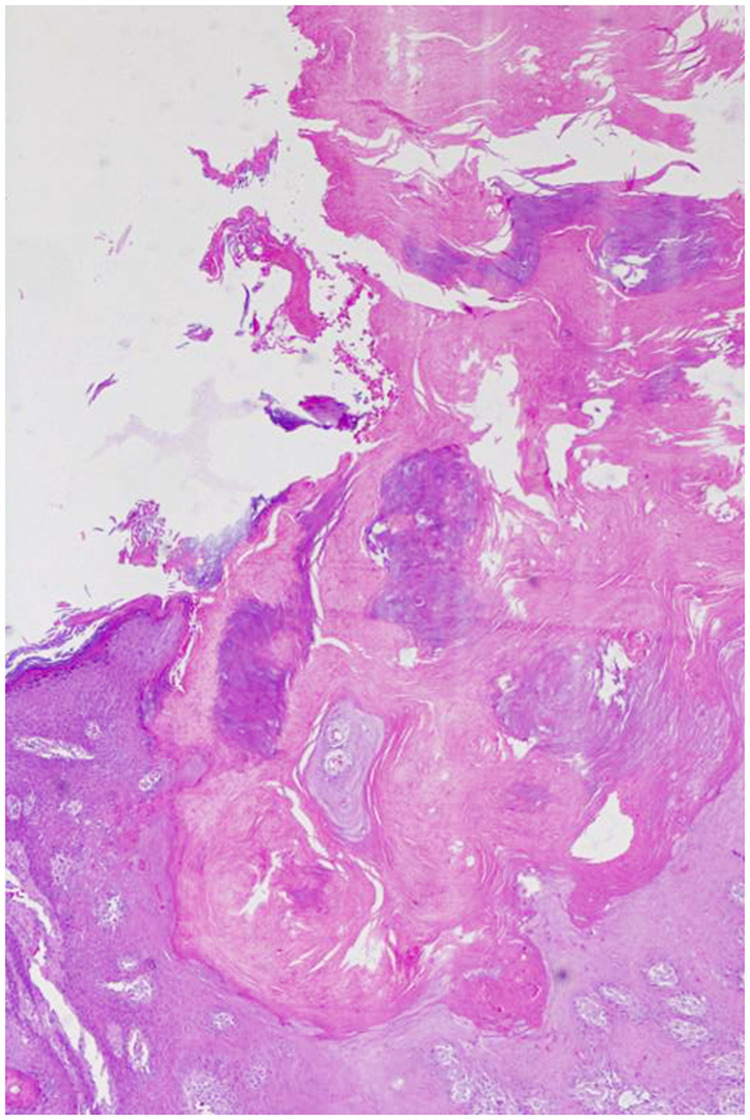

65岁亚洲男性,右小腿屈肌侧出现圆形皮肤病变,首次出现于13岁,并逐渐向周围扩展。在发病前6个月,环状病变上出现深棕色角状角膜病变,质地坚硬,逐渐生长,无疼痛或瘙痒。手术切除皮角,并对环形病变进行活检。病理结果显示真皮胶原蛋白中有丰富的粘蛋白,致密的组织细胞浸润,局灶性轻度胶原变性,确认诊断为环形肉芽肿合并皮角。

A 65-year-old Asian male presented with a circular skin lesion on the flexor aspect of the right calf that first appeared at age 13 and gradually expanded peripherally. Six months prior to presentation, a dark brown, horn-like keratotic lesion with a hard texture emerged on the annular lesion, growing progressively without pain or pruritus. The cutaneous horn was surgically excised, and the annular lesion underwent biopsy. Pathological findings revealed abundant mucin in dermal collagen, dense histiocyte infiltration, and focal mild collagen degeneration, confirming a diagnosis of granuloma annulare complicated by a cutaneous horn.